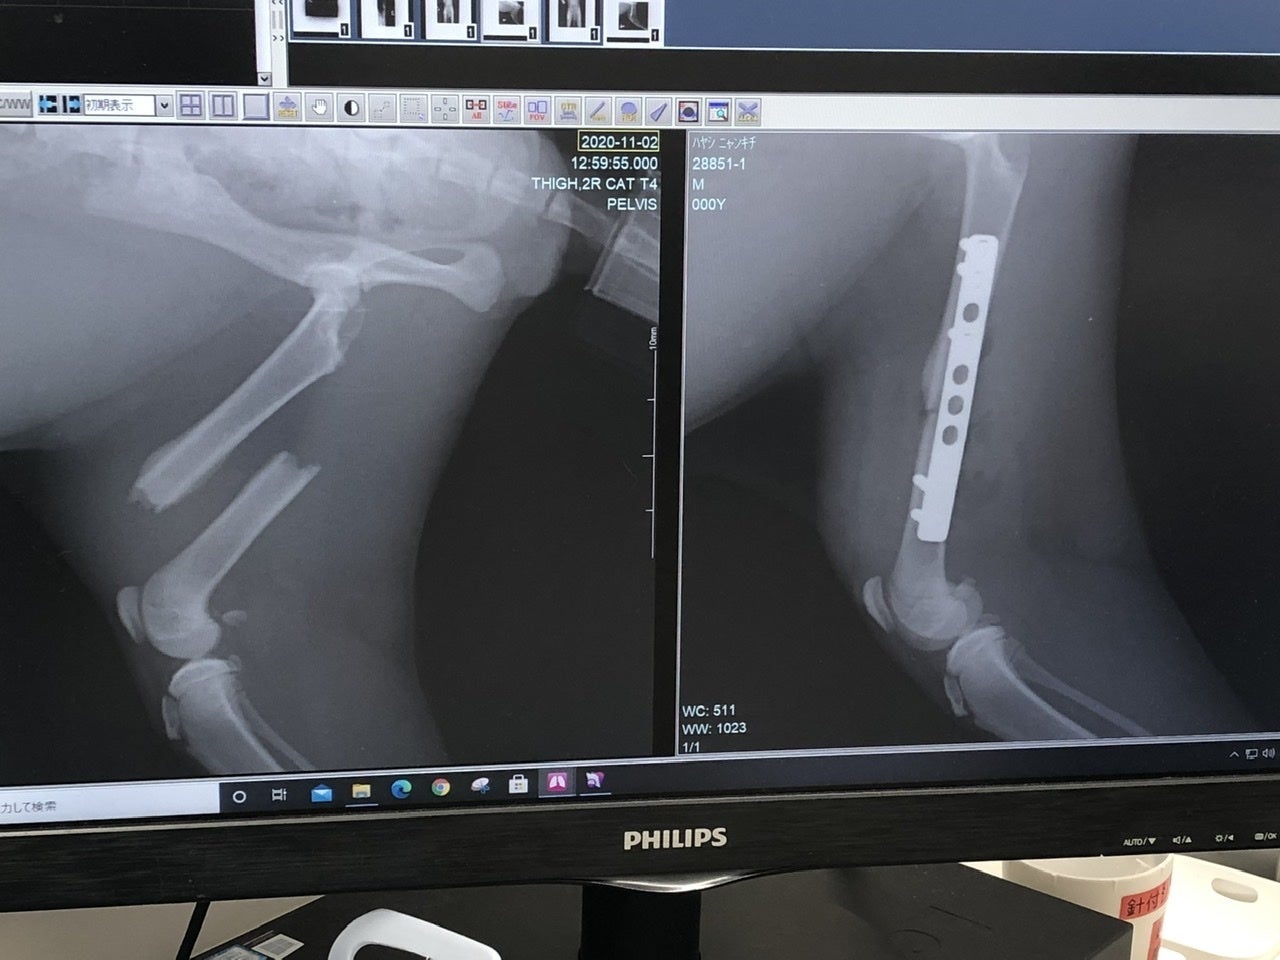

「右上腕部末端(肘)骨折」

「右後ろ大腿骨(付根)骨折」

の2箇所が骨折していました。

それ以外のキズや臓器系、病気などは無く、強い衝撃が生後間もなく右半分に当たり、骨折したものだと、先生がおっしゃられていました。

現在は3カ月ぐらいで、時間の経過と共に骨折した周りの肉(繊維)が固まってきているとの事です。(一度固まった肉を削いで、骨を戻し、金具を入れる)

再度診察の結果、「右上腕部末端(肘)」が、折れた骨の周辺の肉(繊維)が固まってきており、神経が多く通ってる箇所なんで、逆に傷つける恐れがあるとの事で、今回は見送られました。徐々にですが体重もかけれるのと、後ろが治れば負担も少なくなるとの見解です。

「右後ろ大腿骨(付根)」は肉を剥がして奥まで入った骨を戻し、固定の金具をつけます。

次に金具を入れて固定した画像。The 骨折画像と比べると、本当に綺麗に固定されていました。でもまあ、よくこんな折れた状態で店まで、歩いてきたなと。